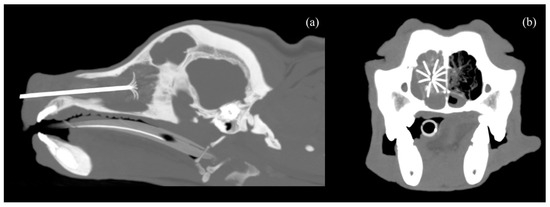

| Variable | Time | Mean | SD | min | Q1 | Q2 | Q3 | Max | p-Value w |

|---|---|---|---|---|---|---|---|---|---|

| HU | T0 | 98.2 | 6.6 | 87 | 95 | 98 | 101.5 | 110 | 0.001 |

| T1 | 60.9 | 9.4 | 50 | 52.5 | 61 | 67.5 | 78 | ||

| Attenuation reduction (%) | 37.6 | 11.1 | 11.4 | 32.4 | 38 | 46.1 | 51.8 | ||

| Volume (cm3) | T0 | 25.2 | 11.1 | 12.3 | 17.0 | 19.5 | 35.7 | 43.8 | 0.001 |

| T2 | 4.4 | 2.7 | 2.2 | 2.6 | 3.2 | 4.8 | 11.2 | ||

| Volume reduction (%) | 82.8 | 4.5 | 74.4 | 81.5 | 83.1 | 84.7 | 9.1 | ||